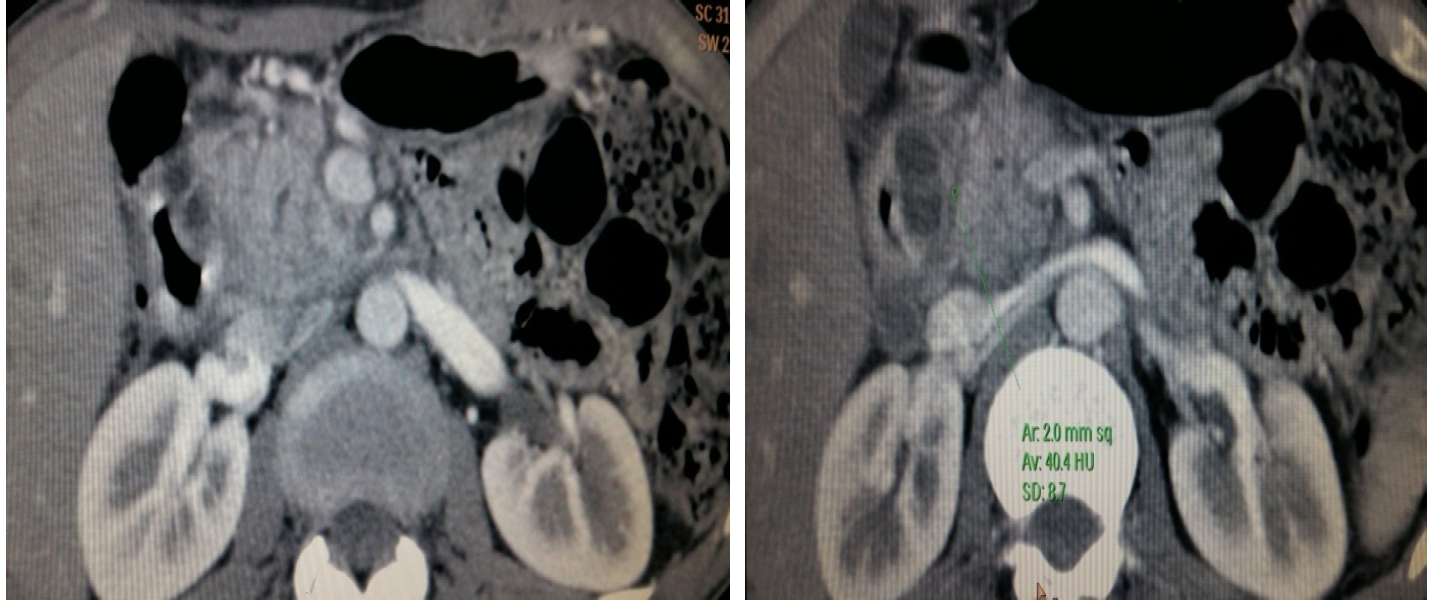

A 40yr old male with history of repeated episodes of the abdominal pain with nausea, vomiting and weight loss of 3 kg in past 4 weeks was referred to radiology department for CECT abdomen. The patient was a smoker with history of alcohol abuse. His serum amylase and lipase levels were raised. CECT abdomen of the patient was done which showed enlargement of the pancreatic head with loss of fat planes between the duodenum and the pancreas. Ill defined hypo enhancing soft tissue was seen in the pancreaticoduodenal groove with thickened medial wall of the duodenum.There was presence of duodenal wall cyst along the medial border leading to the narrowing of the lumen of duodenum. The main pancreatic duct was dilated. CBD was normal in its caliber.Body and tail of pancreas was normal in size and post contrast CT attenuation.Based on these findings diagnosis of the segmental form of groove pancreatitis was made. Diagnosis of pure form of groove pancreatitis was excluded because of involvement of the pancreatic head.

Other differential diagnosis that was considered was of pancreatic head malignancy ,but imaging finding of bulky head of pancreas, thickened medial wall of duodenum, duodenal wall cyst, dilated pancreatic duct, well maintained peripancreatic vessels without any signs of thrombosis and infiltration were more in favour of diagnosis of groove pancreatitis.

Figure 1: (a, b). Axial CECT Imagesshowing Enlargement of the Pancreatic Head with Loss of Fat Planes between the Duodenum and the Pancreas. Ill Defined Hypoenhancing Soft Tissue is also Seen in the Pancreaticoduodenal Groove. Medial Wall of the Duodenum is Thickened and there is Presence of Intramural Cyst